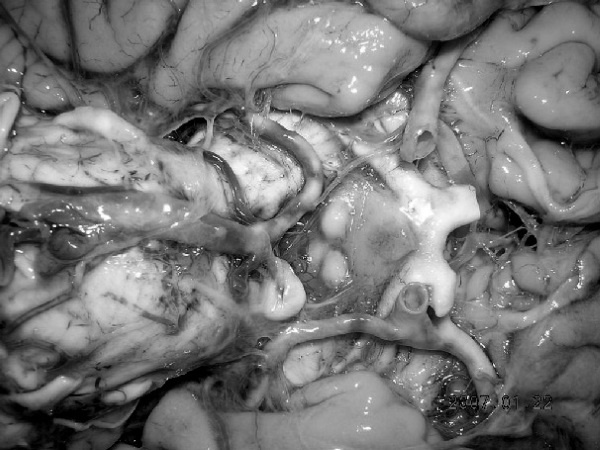

В посмертном эпикризе указан Основной диагноз: последствия ОНМК от 2008 года. ИБС. СН 2. ПИКС. Фоновое: СД 2-го типа, сопутствующее: хронический пиелонефрит. Осложнения: внебольничная пневмония. На секции: ![]() Рис. 31. Последствия перенесенного ОНМК ![]() Рис. 32. Атеросклероз церебральных артерий ![]() Рис. 33. Постинфарктный кардиосклероз ![]() Рис. 34. Гипертрофия миокарда левого желудочка ![]() Рис. 35. Признаки ХСН: мускатный фиброз печени ![]() Рис. 36. Пневмония ![]() Рис. 37. Признаки хронического пиелонефрита Анализируя данный клинический пример, необходимо отметить следующее. 1. Социальный статус. Социальный статус, за исключением указания на участие в ВОВ, не обозначен. 2. Наблюдение на дому. Полное несоблюдение регламента наблюдения ДИП. Клинический диагноз. Записи в амбулаторной карте нет. При этом диагноз должен быть следующим. Основной: последствия ОНМК от 2008 года. ИБС. Постинфарктный кардиосклероз. Фоновое: гипертоническая болезнь 3-й ст., 3 ст. риск 4. СД 2-го типа. Осложнения: длительная иммобилизация. Внебольничная пневмония. НК 2. Хронический пиелонефрит. Анемия. 3. Обоснованность назначения лекарственных препаратов. Терапия СД проводилась вне соответствия с клиническими рекомендациями, контроль за уровнем гликемии не осуществлялся, лечение анемии отсутствовало, вместе с тем при отсутствии подтвержденных данных за пиелонефрит были назначены антибиотики. Таким образом, наряду с указанными замечаниями врач не оценил тяжесть состояния, что не позволило решить вопрос о показанной госпитализации. Приложение № 6 – алгоритм лечения анемии. Приложение № 7 – самоконтроль уровня глюкозы. Пациентка Ф., 84 года. Умерла в январе 2011 года. Иммобилизирована с марта 2010 года в связи с закрытым переломом лонной и седалищной костей. В карте ежемесячные осмотры терапевта в связи с активами СМП. Причина вызовов: гипертонические кризы и болевой синдром. За год до смерти проведены доступные на дому анализы. В плановом порядке в апреле 2010 году проходила стационарное лечение в терапевтическом отделении. Диагноз при выписке: дисциркуляторная энцефалопатия 2-й ст. ГБ. ИБС. СН 3. ПИКС от 2001 года. Железодефицитная анемия. Закрытый перелом лонной и седалищной костей справа. Амбулаторно после стационара принимала энап Н и винпоцетин. В посмертном эпикризе указан Основной диагноз: 1) дисциркуляторная энцефалопатия 2-й ст. и ИБС. СН 3. ПИКС от 2001 г. НК 2А. Фоновое: ГБ. Сопутствующее: хроническая железодефицитная анемия. Закрытый перелом лонной и седалищной костей от 11.03.2010. ![]() Рис. 38. Повторный инфаркт головного мозга ![]() Рис. 39. Постинфарктный кардиосклероз ![]() Рис. 40. Атеросклероз коронарных артерий ![]() Рис. 41. Проявления НК: мускатный фиброз печени ![]() Рис. 42. Острые эрозии желудка ![]() Рис. 43. Атеросклероз аорты Замечания к ведению больного следующие: 1. Социальный статус. Информации нет. 2. Наблюдение на дому. Посещение терапевта осуществлялось только в связи с активами СМП. 3. Клинический диагноз. Нет правильной формулировки диагноза. При этом правильный диагноз был бы следующим. Основной диагноз: 1) Повторный инфаркт головного мозга. 2) ИБС. Постинфарктный кардиосклероз от 2001 года. Фоновое: гипертоническая болезнь 3 ст., 3 ст. Осложнения: закрытый перелом лонной и седалищной костей от 11.03.2010. Длительная иммобилизация. НК 2. Острые эрозии. Хроническая железодефицитная анемия. Сопутствующие: атеросклероз аорты. 4. Обоснованность назначения лекарственных препаратов: лекарственная монотерапия ГБ эналаприлом неэффективна, что повлекло за собой неоднократные гипертонические кризы и вызовы СМП, нет лечения проявлений ПИКС и анемии. Таким образом, не было оценки тяжести состояния, наличия тяжелой степени АГ у больной с перенесенным ОНМК и инфаркта миокарда, кризовым течением и признаками СН, что требовало госпитализации пациента. Приложение № 8 – ведение больного, перенесшего инфаркт миокарда. Пациентка Б., 95 лет. Иммобилизирована. Карта малоинформативна. Осмотры терапевта 1–2 раза в год, лист впервые выявленных диагнозов не ведется. Анализы отсутствуют. Известно, что наблюдалась с диагнозом ИБС, ЦВБ. Хронический бронхит. ОНМК с левосторонним гемипарезом и перелом шейки бедра без указания давности. В карте имеются указания на пролежни. За последние 2 года до смерти терапевтом были назначены: пирацетам, предуктал, мексидол, проведен курс ЛФК на дому. Посмертный эпикриз отсутствует. На секции: ![]() Рис. 44. Последствия перенесенного инфаркта головного мозга ![]() Рис. 45. Постинфарктный кардиосклероз |